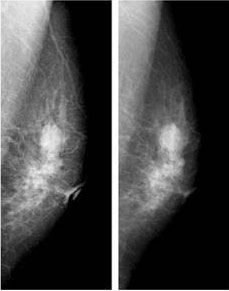

fig7 乳房X線写真の差

Fig.7に臨床画像の一例を示します(滋賀医科大学提供)。被写体線量が同一の撮影でえられたPCM画像(左)と従来のSF画像(右)とを比べると、PCM画像では乳房構造が鮮明に描写されていることがわかります。そして、多くの臨床画像の検討の結果、乳房X線写真(マンモグラフィ)の使命とも言われる微小石灰化像の描出性は、従来のSF画像以上であると評価されるに至りました。

今後、このシステムが乳癌の早期発見に貢献することを期待して止まない。